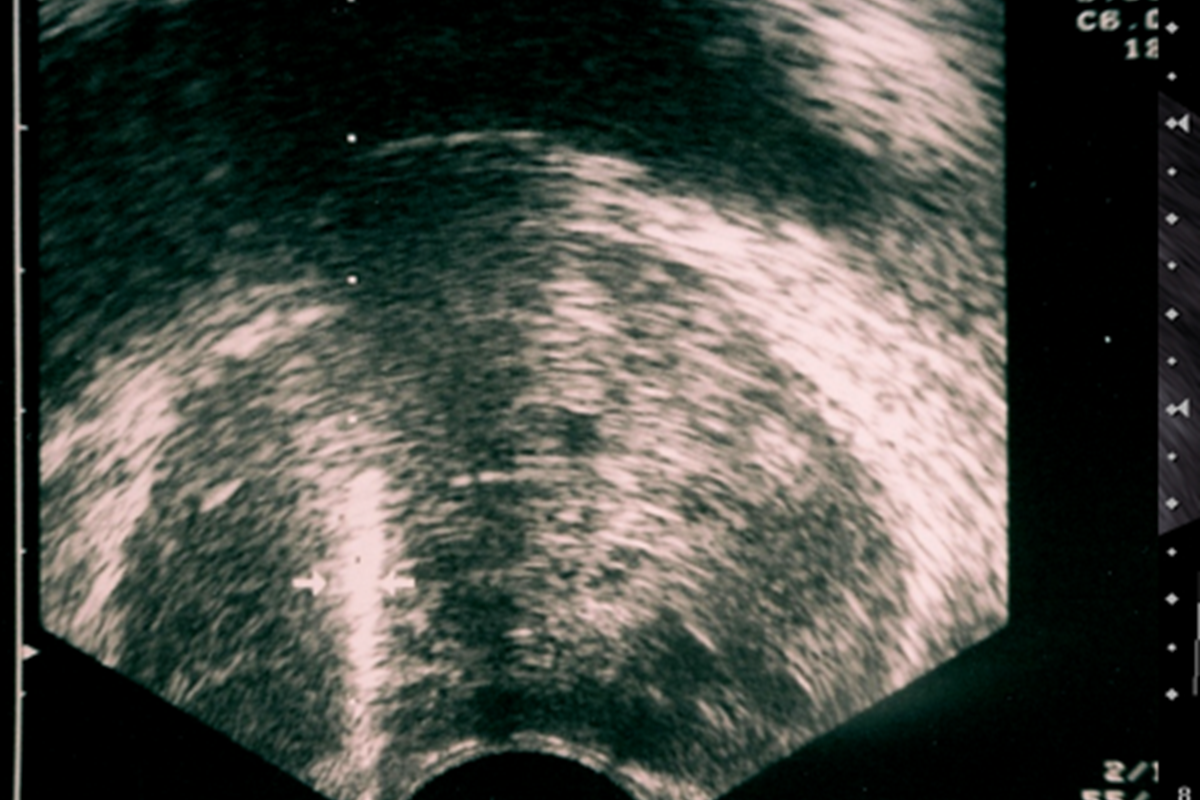

Başlığı makat bölgesine yerleştirdikten sonra, Ultrason’da prostat çok net olarak görülür. Önce, çok ince bir iğneyle prostat çevresine uyuşturucu ilaç verilir. Böylece prostat uyuşur ve işlemin bundan sonraki kısmını hasta sadece sinek ısırığı gibi hafif bir acı olarak hisseder. Ultrason ile prostat görülürken, özel bir iğne ile prostatın içinden parçalar alınır. TRUS prostat biyopsisinde, genellikle prostattan 12 adet parça alınmaktadır. PSA’sı çok yüksek olan hastalarda bu sayı azalırken, prostatı çok büyük olan hastalarda, tekrar biyopsilerde veya şüpheli odak görülen biyopsilerde alınan parça sayısı 14-18’lere kadar çıkabilir. İşlem yaklaşık 15 dakika kadar sürer ve yukarıda da bahsettiğimiz gibi, hastamız çok az ağrı hissederek işlemi tamamlar.